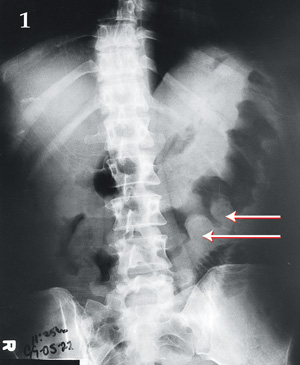

Bowel wall "thumbprinting" in pseudomembranous colitis

Med J Aust 2003; 179 (2): 107. || doi: 10.5694/j.1326-5377.2003.tb05448.x